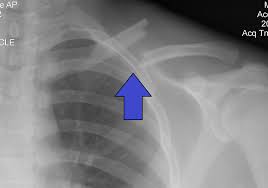

In skeletal traction, a pin (eg, a Steinmann pin) is placed through a bone distal to the fracture. Weights are applied to this pin, and the patient is placed in an apparatus to facilitate traction and nursing care. Skeletal traction is most commonly used in femur fractures: A pin is placed in the distal femur (see the image below) or proximal tibia 1-2 cm posterior to the tibial tuberosity. Once the pin is placed, a Thomas splint is used to achieve balanced suspension.